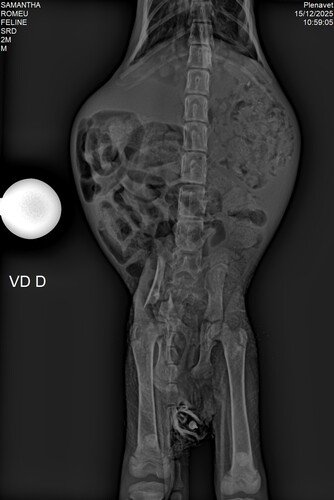

Quando a vida apertou, o Madruguinha fez como o Seu Madruga: contou com a solidariedade de quem pudesse estender a mão. Com apenas dois meses de vida, esse filhotinho foi atropelado e passou a lutar para sobreviver após uma fratura grave na pelve, que comprometeu funções básicas como urinar e defecar.

Foram dias difíceis, de incerteza e espera. No momento mais delicado, quando a ajuda parecia limitada e a desistência foi colocada como opção, escolhemos não soltar sua patinha. Entre lares temporários, cuidados constantes, exames, medicamentos e internação, conseguimos chegar ao que parecia distante: a cirurgia ortopédica.